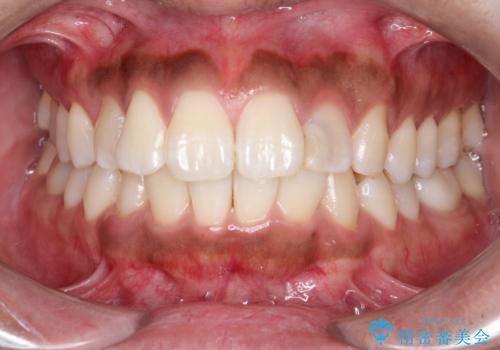

- 「前歯の歯の色が気になる」を主訴に来院された患者さんです。歯の大部分がプラスチックの材料で治療されていました。そこが劣化し変色していたためオールセラミッククラウンで治療を行いました。前歯の色を全体的に白くするために当院でオフィスホワイトニングも行いました。

左上2番の大部分がプラスチックの材料で治療されていました。そのプラスチックの材料が劣化して変色し虫歯になっている状態でした。なので古いプラスチックの材料を全て除去し、その下の虫歯を取った後、オールセラミッククラウンで治療を行いました。オールセラミッククラウンを装着する前に当院にてホワイトニングを行いました。